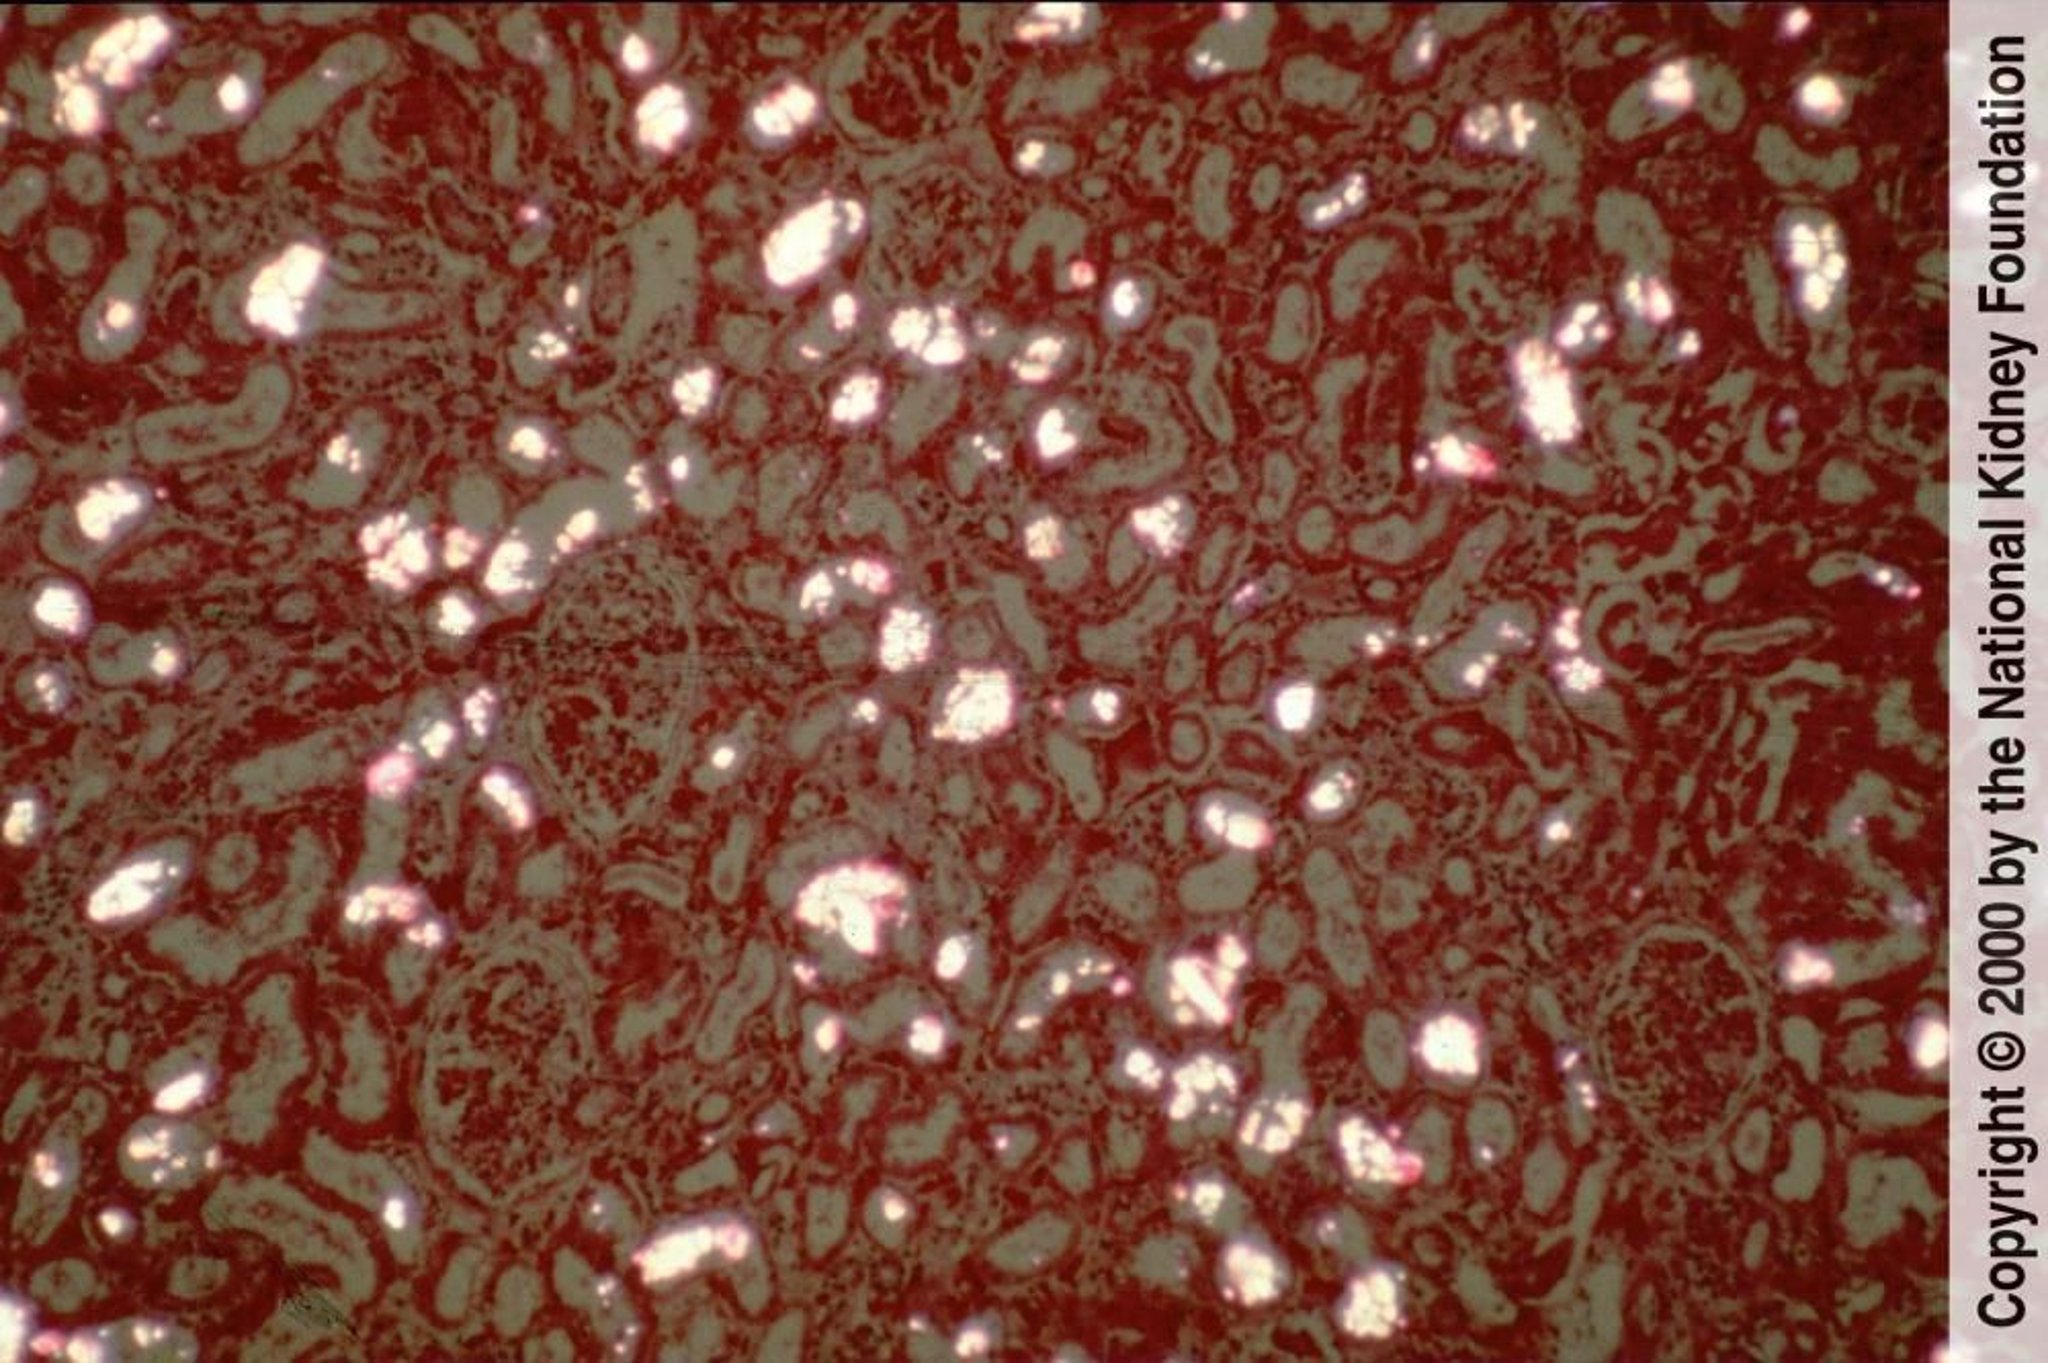

Гипероксалурия

Кристаллы оксалата кальция осаждаются в почечных канальцах и легко видны в виде двулучепреломляющих и веерообразных или сноповидных кристаллов при поляризованном свете (поляризованный гематоксилин-эозиновый краситель, ×100).

Image provided by Agnes Fogo, MD, and the American Journal of Kidney Diseases' Atlas of Renal Pathology (see www.ajkd.org).